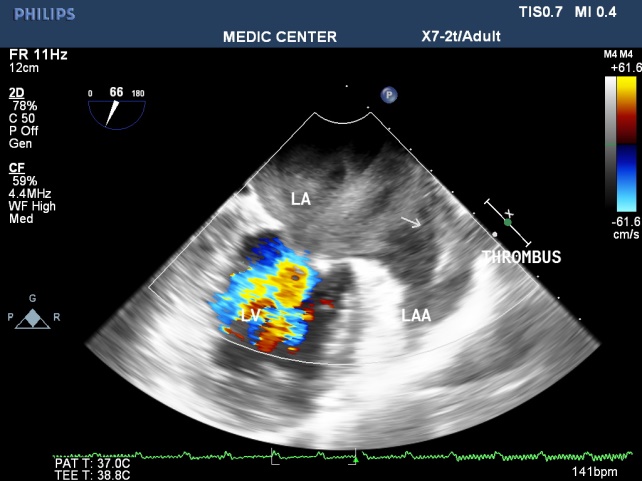

Because patients often presented late in Hospitals, their Wilkins score usually is high (68% with Wilkins score is superior to 8). Especially, LAA thrombus, even small size, furthermore, can be detected more clearly on RT- 3DTEE. Volume and mobility of LAA thrombus appreciated better on 3DTEE.

Detection LA and LAA thrombus by RT-3DTEE is more sensitive than 2DTEE with X-plane mode and 3 D Zoom only are avaible in 3DTEE.

Figure 2. LAX view showing MS with severely calcified mitral leaflets& presence of LA thrombus

Figure 9. MS with spontaneous contrast and thrombus in LA& LAA, 2DTEE plane of 60°

Figure 15. 2DTEE presenting LAA thrombus